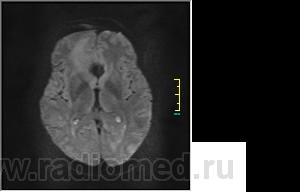

Пациентка направлена на исследование с диагнозом "Гипертонический криз", энцефалопатия неуточненная.

DWI:

частично функционирующая аневризма

Иначе говоря, аневризма с хронической геморрагией, т.к. мы видим фракции крови различного возраста.

Постепенное пристеночное образование тромбов приводит к появлению типичного для аневризмы феномена -слоистости МР сигнала в полости аневризмы. Данная картина демонстрирует слоистый характер тромботических масс в полости аневризмы .Функционрирующая часть имеет низкий сигнал во всех режимах сканирования. Дополнительно-перифокальный отек.

А может более корректно интерпретировать как частично тромбированная аневризма... Уж коь речь идет о фракциях, ну то есть о тромбе по сути.... Ну и плюс перфокальный отек головного мозга (вероятнее цитотоксический+вазогенный).